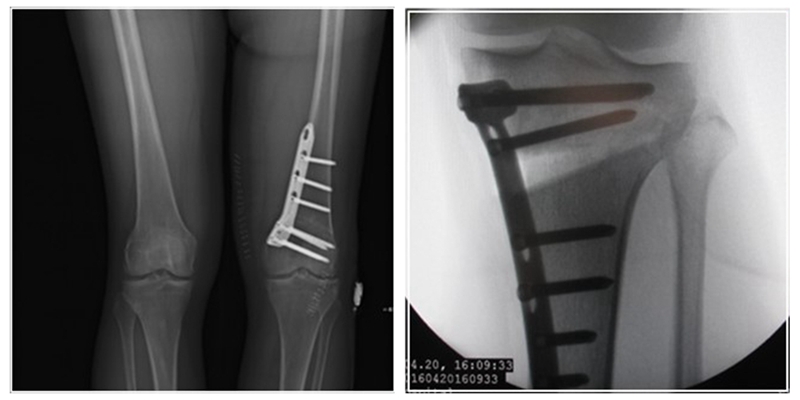

术后影像

股骨胫骨双截骨的手术策略

1、手术方式

股骨畸形矫正:采用内侧闭合截骨或外侧闭合截骨。

胫骨畸形矫正:尽量采用内侧开放截骨术,部分特殊情况可以采用内侧闭合或外侧闭合楔形截骨术。